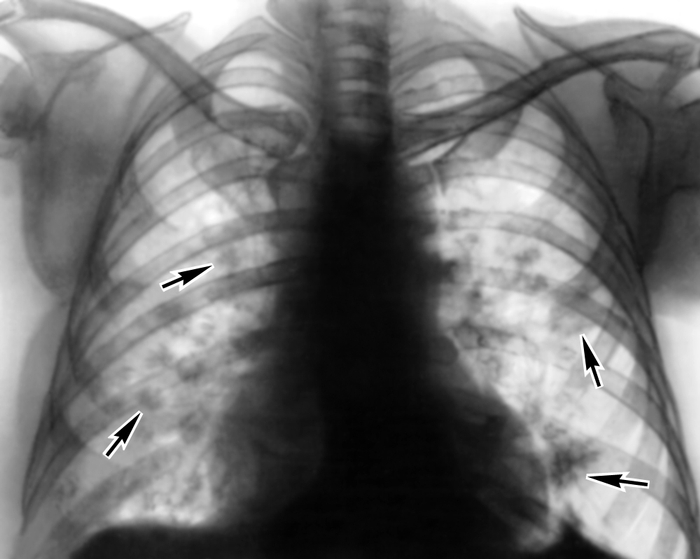

Симптомы и причины скопления воды в легких

Раздел: Ракурсы просвещения